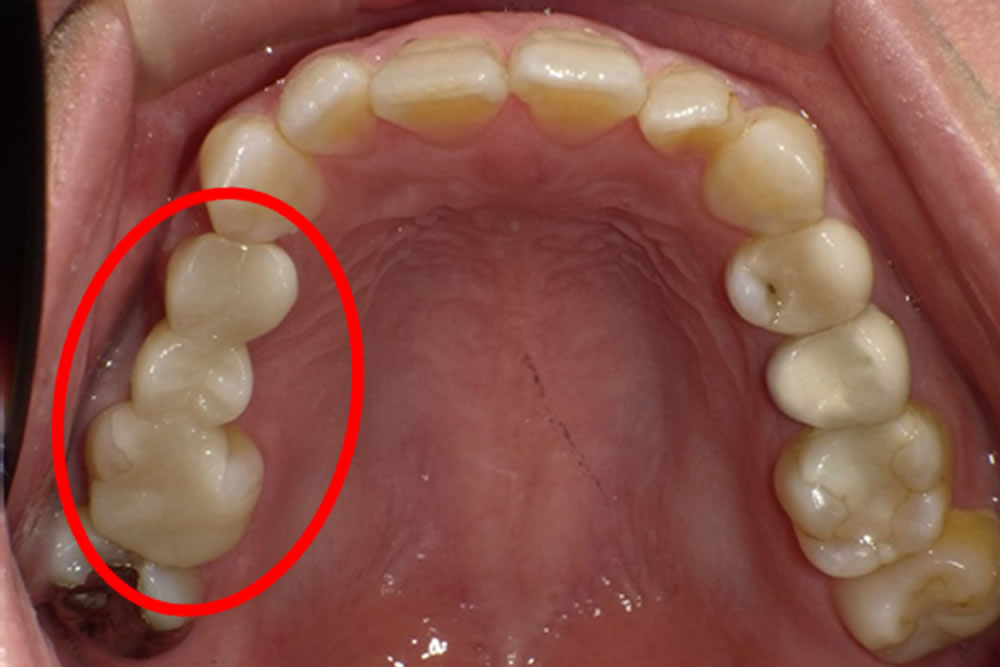

こちらの患者さまは他院で入れたブリッジの土台の歯(4番目の歯)の歯茎が腫れてきてしまったため、治療を行うことになりました。

完成したセラミックブリッジを装着して治療完了です。ご自身の歯に近い色味で作製したため、境目がほとんど分からないほど自然で綺麗に仕上がりました。患者さまにも仕上がりにご満足いただけました。